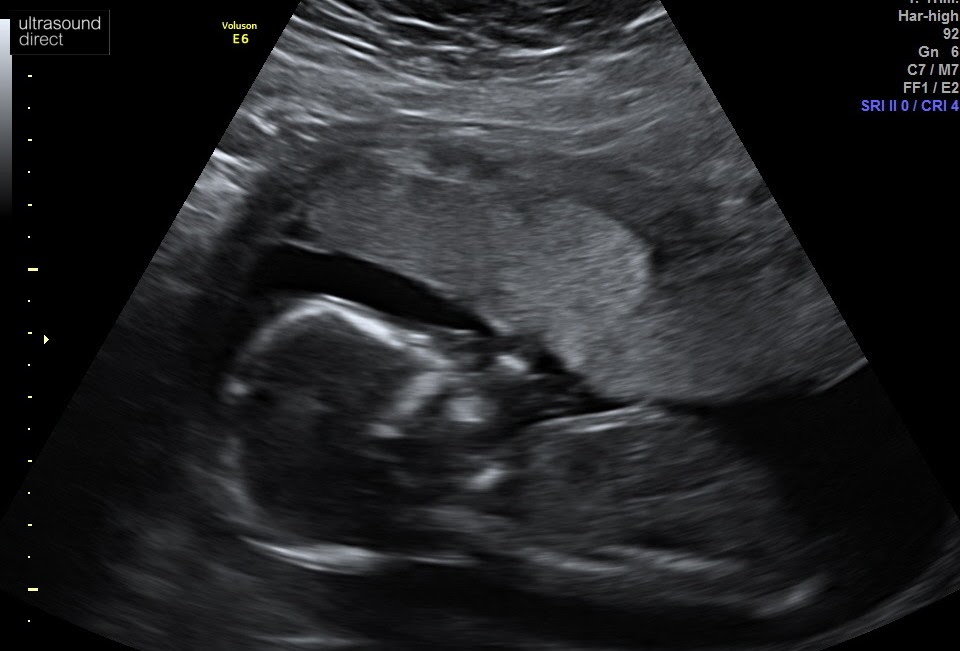

Bump at 17 weeks

Private scan at 17 weeks

Before I knew it, we were having a private gender scan, simply because Ash (no one) was allowed to the NHS appointments and I didn’t want to find out the gender without him. Not that he was all that bothered and he definitely was not excited to learn that the new baby was a girl..

I was over the moon and felt like the luckiest girl alive in that moment. I had one healthy and happy little boy, our Caleb. Then on the way I had a healthy baby girl! On the face of it, I had/have it all. The children, the husband, even a little yappy dog who lives in the house with us in our nice neighbourhood. On the surface I am happy, I smile, I laugh and joke at the right times. It’s all very superficial though.